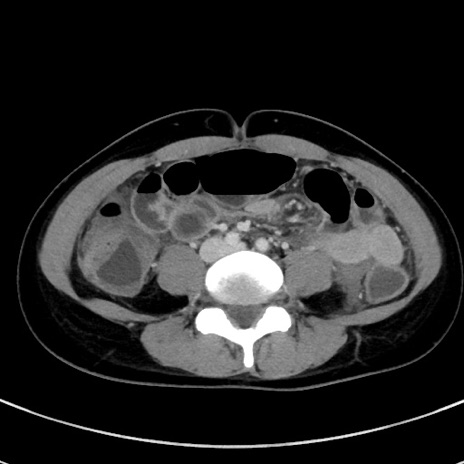

症例17(横断像)

【症例】20歳代女性

【主訴】嘔吐、下腹部痛

【現病歴】昨日夕食後に嘔吐し下腹部痛が出現。本日になっても嘔吐持続し改善しないため来院。

【身体所見】意識清明、BT 37.2℃、BP 108/67mmHg、腹部:平坦、やや硬、下腹部正中から右にかけて圧痛あり、反跳痛軽度あり、tapping pain(+)。

【データ】WBC 13600、CRP 14.94